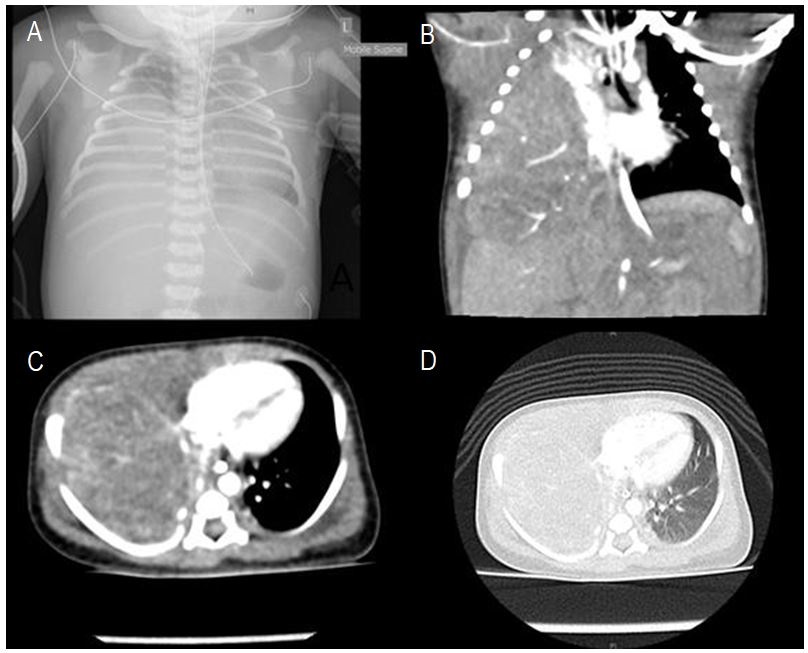

Figure 1

(A) Chest X-ray of Case 1 on Day 1 of life showing a homogenous opacity in the right hemithorax associated with mediastinal shift to the left. (B) Coronal view of CT chest with a contrast of Case 1 on Day 2 of life showing solid appearing lesions in right hemithorax without air-filled components. (C) Axial view with abdominal window (D) Axial view with lung window.

A female infant was born at 39+6 weeks gestation via vaginal delivery. Apgars at birth were 7 and 9. Antenatal scans showed possible polyhydramnios. After birth, she developed respiratory distress. Chest x-ray (Fig. 1) showed a homogenous opacity in the right hemithorax with only a small amount of aerated lung at the apex with the associated mediastinal shift. She was intubated and then transferred to our specialist pediatric hospital for ongoing management. An ultrasound showed extensive opacity in the right hemithorax due to a large mass with some small cystic spaces. A CT chest with contrast (Fig. 1) demonstrated a solid appearing lesion occupying most of the right hemithorax without any air-filled components. Alpha Fetoprotein and Beta HCG were normal for a neonate. Preoperative echocardiography showed a structurally normal heart, however, pulmonary hypertension was noted. The differential diagnosis at the time included Cystic Pulmonary Adenomatoid Malformation (CPAM) or Pleuropulmonary Blastoma (PPB).